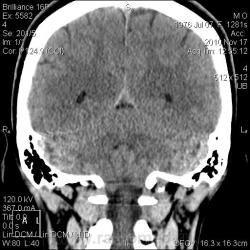

Тип патологии:

Область исследования:

Методы исследования:

- https://radiomed.ru/sites/default/files/styles/case_slider_image/public/user/2841/arnolda-kiari_1_st0002.jpg?itok=md82tYMh